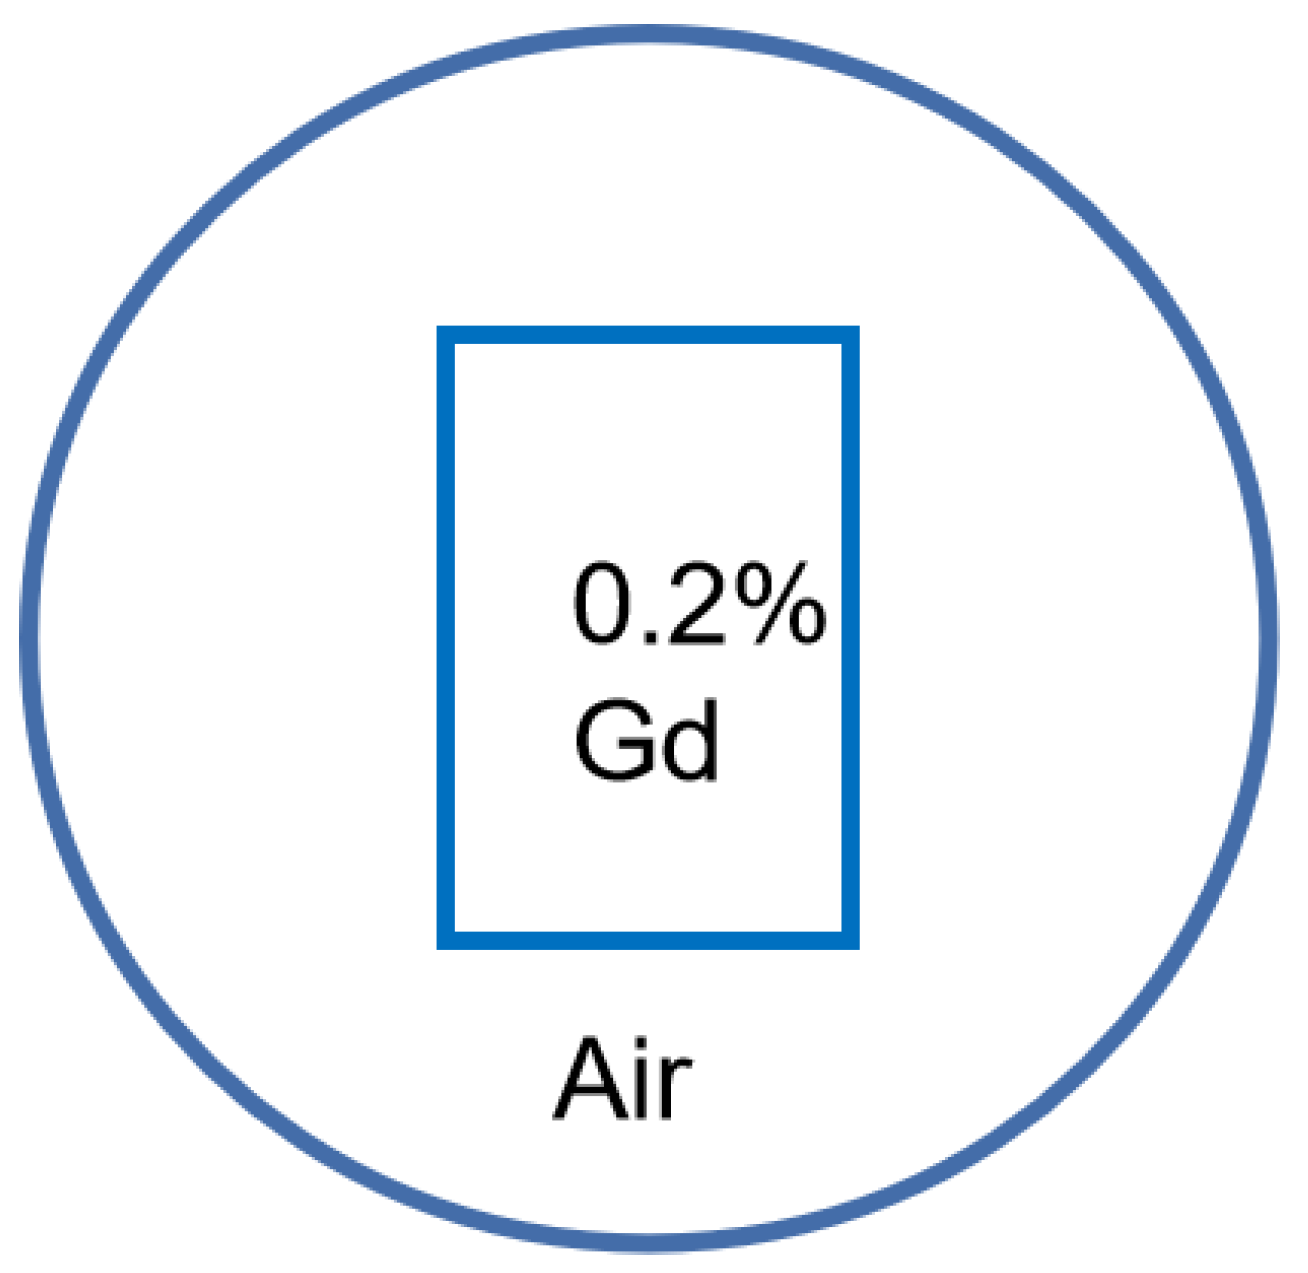

2.3. Datasets